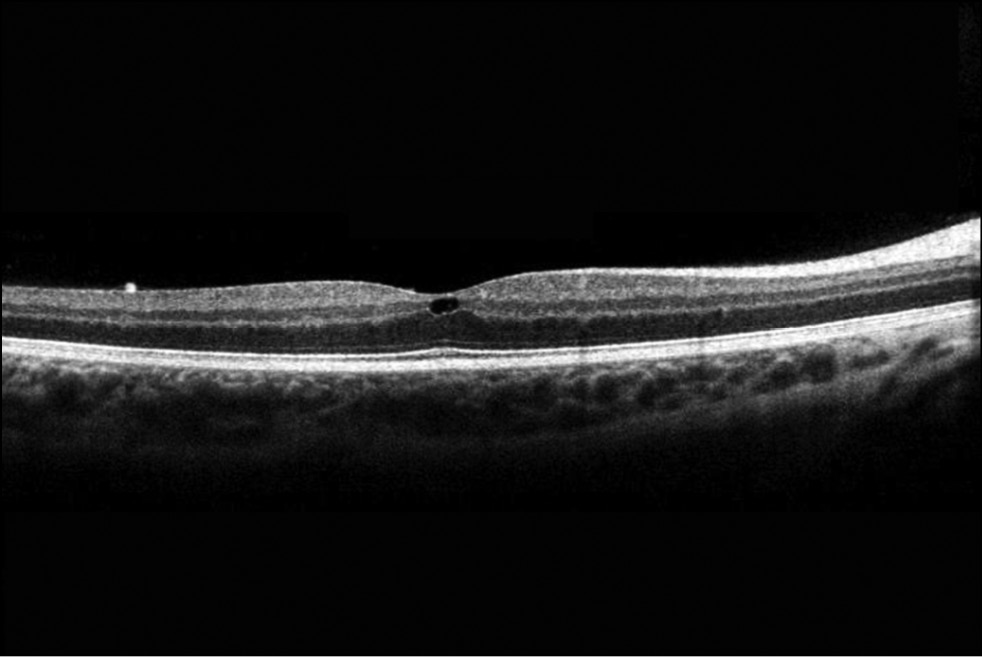

С помощью оптической когерентной томографии на правом глазу в зоне фовеа выявлена микрокиста во внутренних слоях сетчатки, на левом глазу изменений сетчатки в центральных отделах не выявлено (рис. 2).

Рис. 2. Оптическая когерентная томограмма сетчатки OD, гипорефлективная полость на уровне внутренней сетчатки. / Fig. 2. Optical coherence tomogram of the retina OD, hyporeflective cavity at the level of the inner retina.